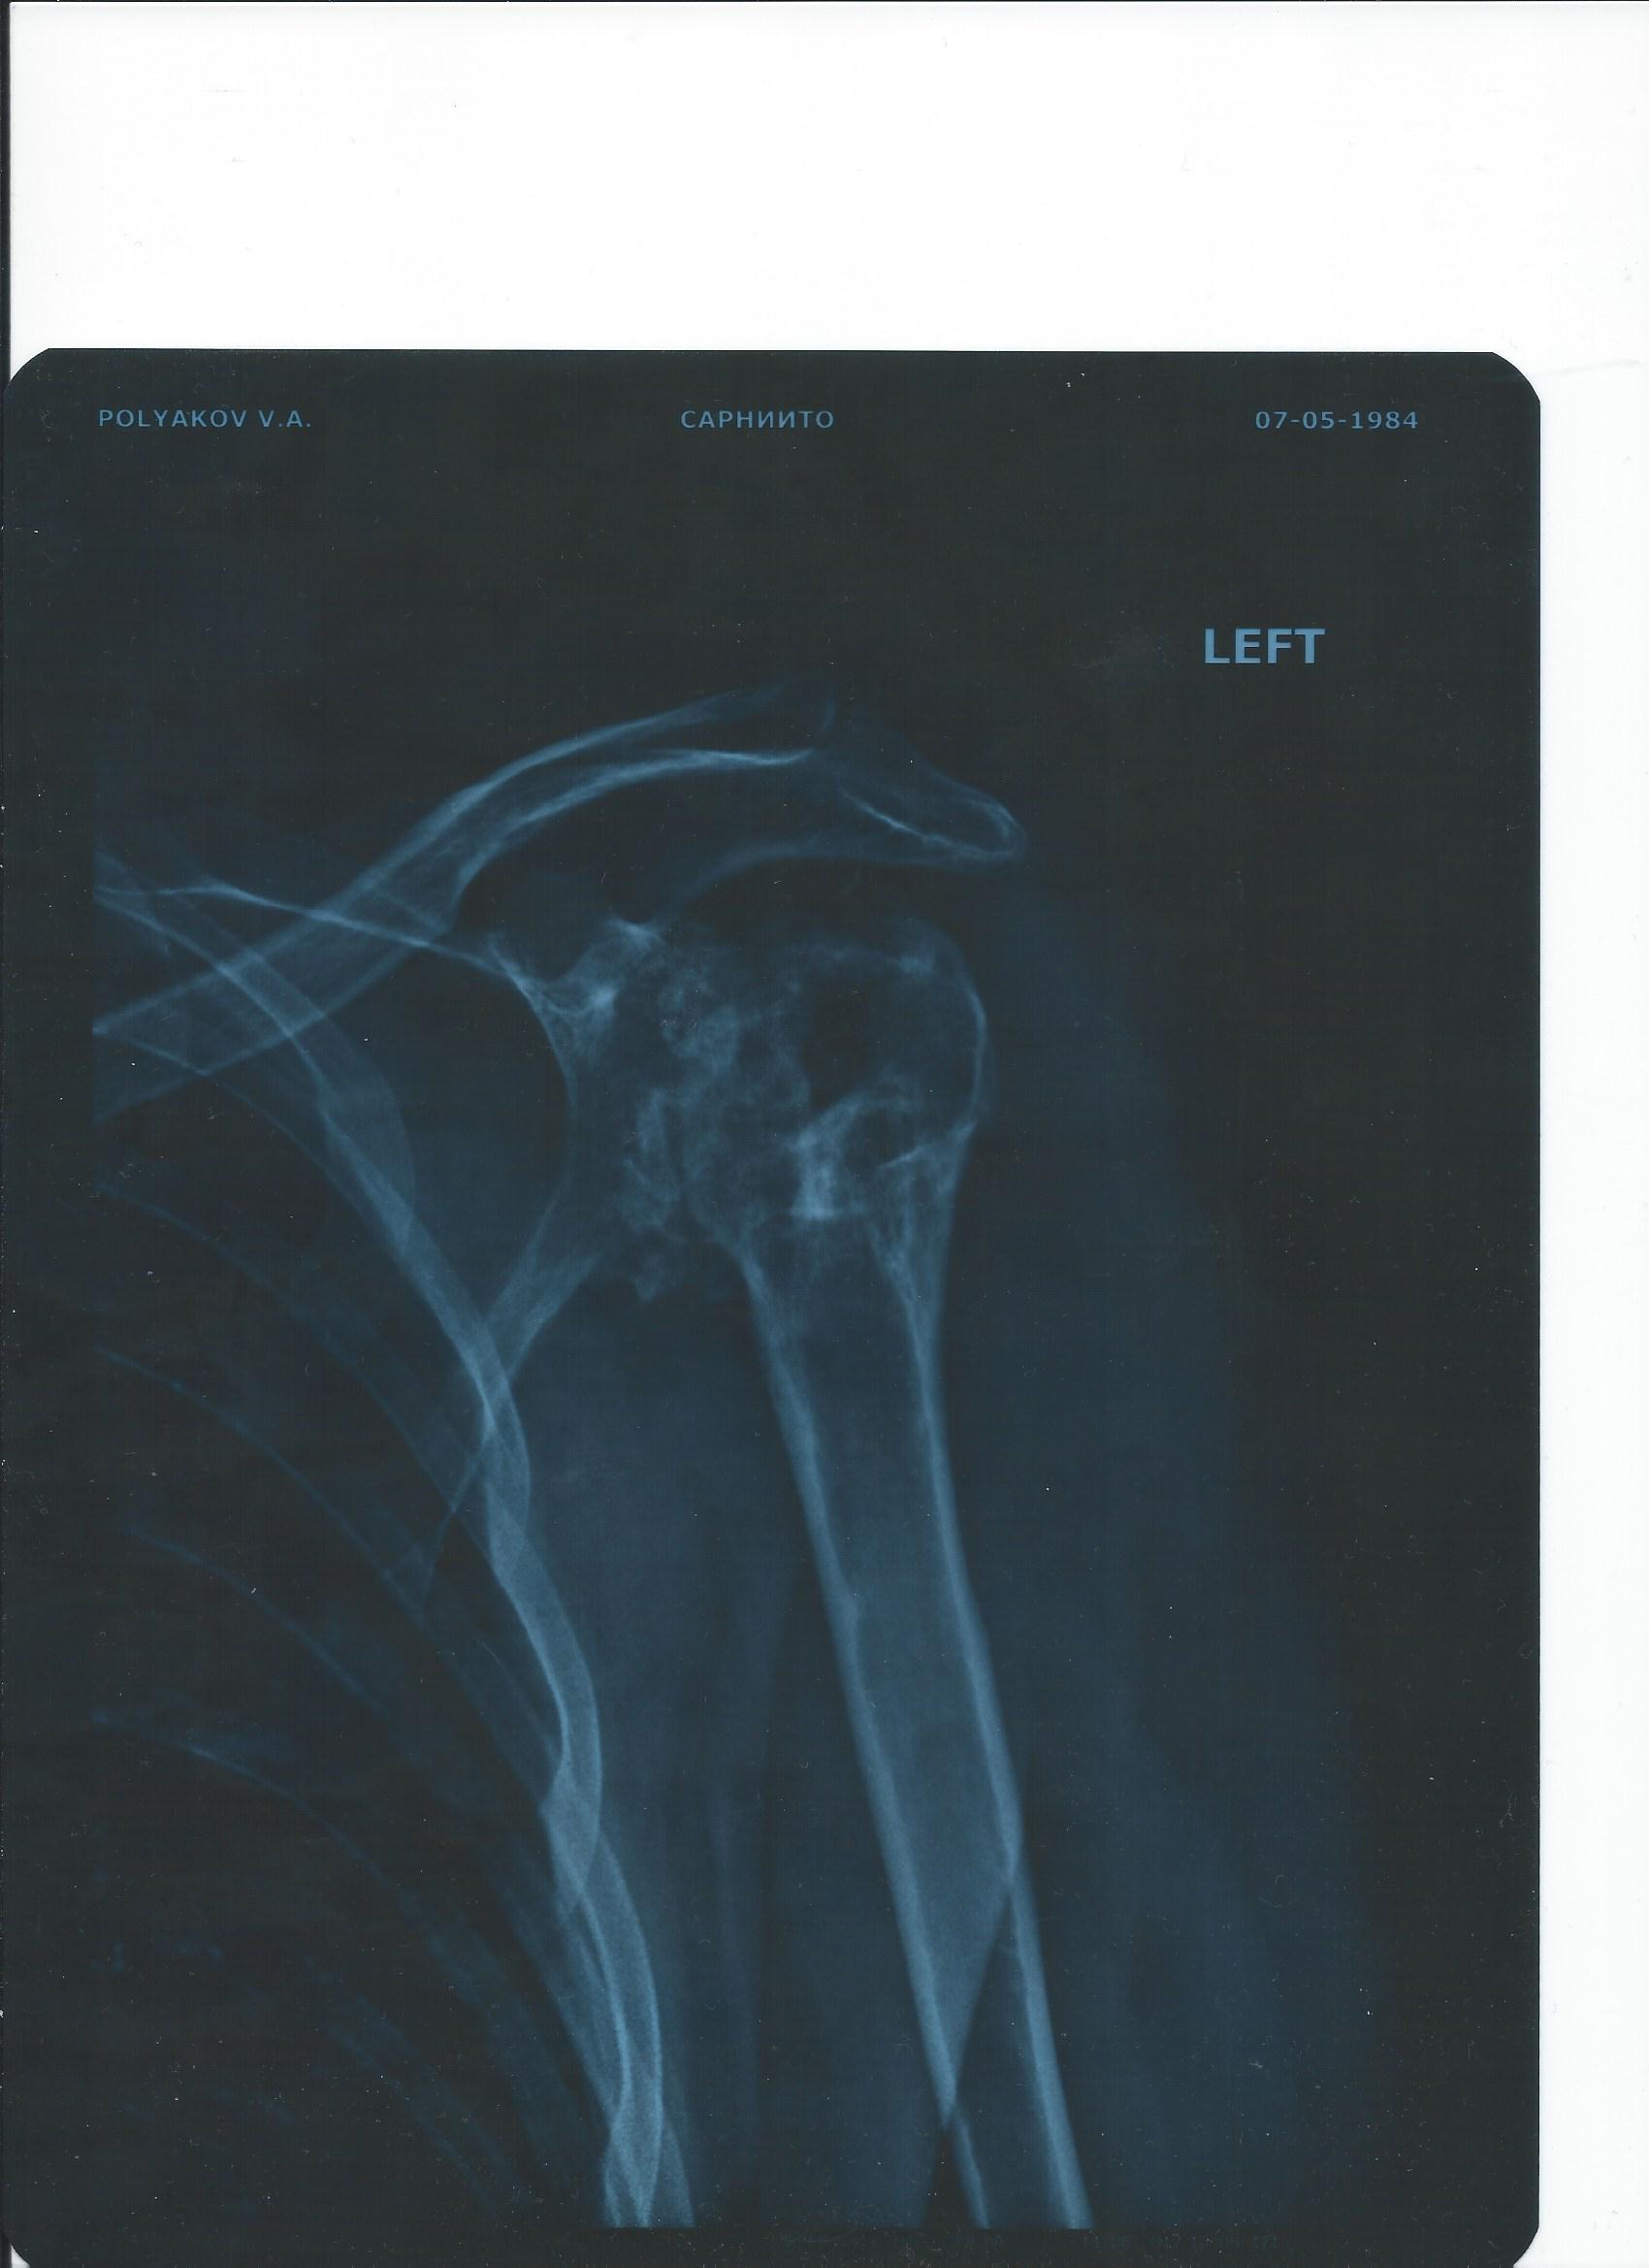

Эндопротезирование плечевого сустава

Здравствуйте, уважаемые доктора!!! Подскажите, пожалуйста, что можно сделать в моей ситуации: начиная от консервативного лечения и заканчивая эндопротезированием. И где эндопротезирование сделать? Рекомендуют Израиль и Германию, но без конкретики.

• Кликните для загрузки файла Ro.jpg